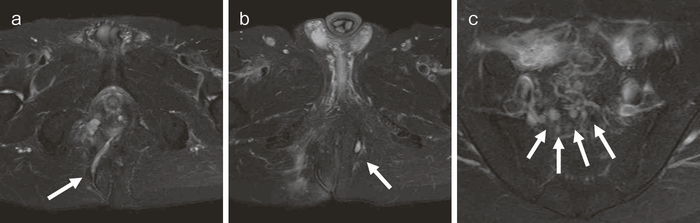

(1)体位,生検部位(図23)

全身麻酔下に,砕石位もしくはJack-knife位で行う。生検を行う部位は,歯状線付近を全周性に3カ所程度行う。

(2)手 順(図24)

視診,触診,直腸診で診察を行う(図24a)。診察でターゲットとなる部を認めた場合は,その部位から生検し,ない場合は肛門鏡で視野を確保し,歯状線近傍から全周性に3カ所ほど行う(図24b)。痔瘻を伴う場合は,非活動性,瘢痕化している場合でも,瘻管内から生検を行う(図24c)。

(3)狭窄病変がある場合(図25)

小指,示指で愛護的に拡張した後(図25a),ブジーを使って,内視鏡検査が可能な程度まで拡張を行う(図25b)。内視鏡により直腸の観察,生検を併せて行う(図25c,d)。

図23 肛門管粘膜,瘻管内からの生検